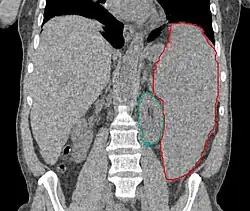

• Normal spleen in adults measures 8-13 cm and is typically not palpable. Weight 150-250 g

• Splenomegaly

• Multiple causes: inflammation/infection (increase in white pulp), congestive expansion (increase in red pulp), increased blood pool, increased macrophage activity, proliferative cellular infiltration, extramedullary hematopoiesis, storage diseases, cysts, solid tumors (primary rare, solitary met from colorectal, ovarian)

• Patients should be continuously monitored, and fields adjusted with shrinking spleen